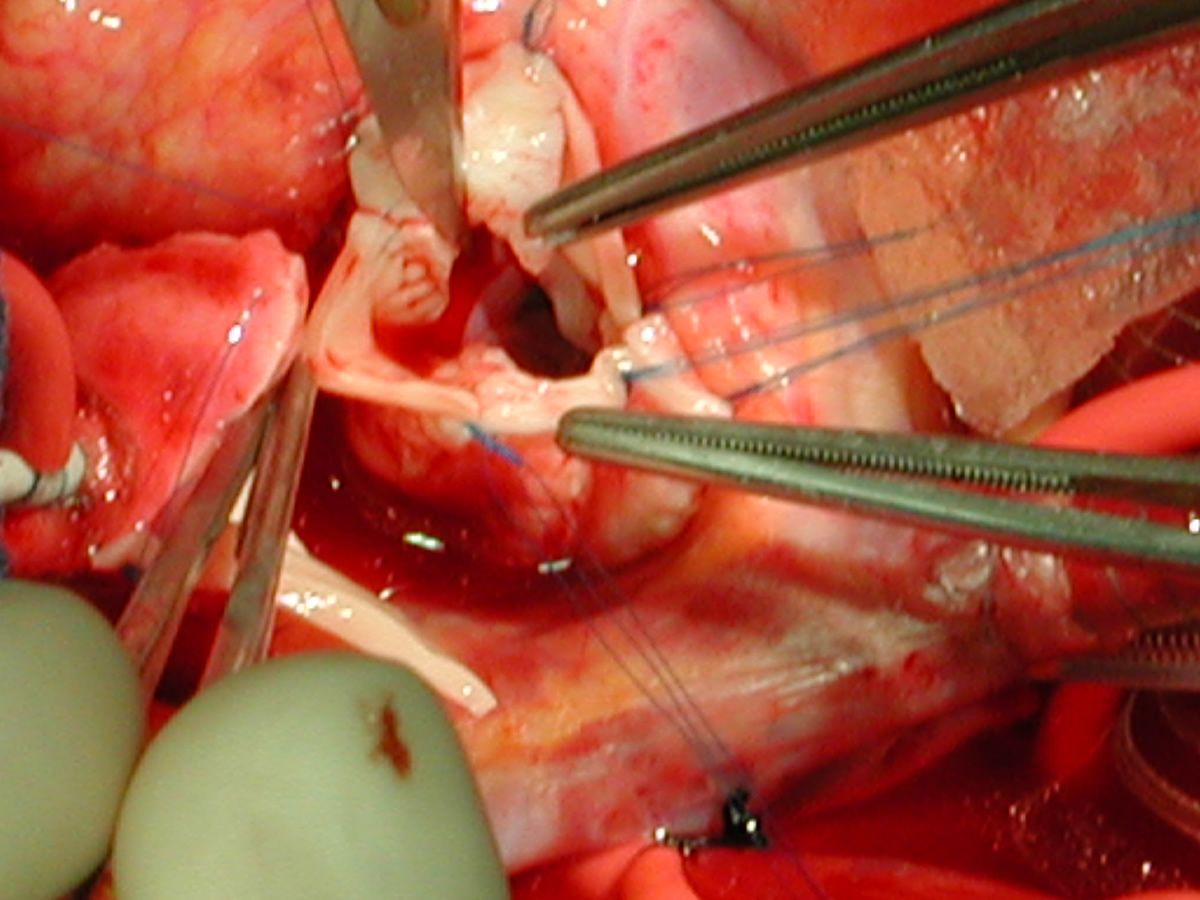

Figures 24 & 25: An incision is performed in the distal ascending aorta so that the orifice of the completed distal reconstruction will correspond in size to the proximal reconstructed aorta. Figures 26 & 27: A shield-shaped patch is being placed in the incision in the proximal ascending aorta – noncoronary cusp. Suturing is with 7-0 polypropylene suture. The patch should not be too wide, becaus this will lead to commissural stretching and loss of central coaptation with reultant aortic valve insufficiency.